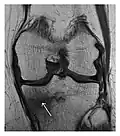

Figure 8: Proximal diaphyseal fatigue fracture of the tibia in a 20-year-old man with a history of regular jogging. (a) Lateral radiograph shows no obvious fracture lines but a subtle localized medial tibial cortex periosteal reaction (arrows). (b) Sagittal reformatted CT image acquired 1-month after the radiograph shows a linear hypoattenuation in the tibial cortex (arrowhead), as well as obvious periosteal thickening (arrows). (c) Sagittal T2-weighted fat-saturated image acquired the same day shows an area of hyperintensity spreading over the proximal tibia (arrows), which is consistent with the presence of proximal tibial fracture.[1]